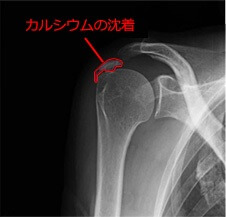

カルシウムが筋肉の腱や靭帯に沈着することで、柔軟性も失われます。

結石や石灰沈着はでるわ…。

- 肩関節石灰沈着症(肩や腕の痛み)

- 石灰沈着性腱板炎(石灰性腱炎)

- 骨粗しょう症、骨石灰化

- 皮膚石灰沈着症

- 動脈硬化、血管が硬くなる石灰化

- 動脈壁や心臓弁などに生じる石灰化・プラークなど

マグネシウム不足はカルシウムによる、硬さ、結石、石灰化、腫瘍化などの「硬くなる系」の症状を和らげることができなくなります。カラダが文字通り石化していくのです。老化がすすみますね。